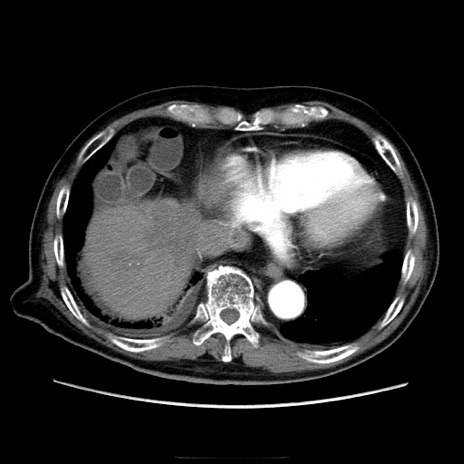

症例21(横断像)

【症例】70歳代男性

【主訴】腹痛

【現病歴】肝硬変・肝細胞癌にてかかりつけの方。約9時間前に食後より腹痛出現。症状が徐々に増悪し、嘔吐出現したため来院。

【既往歴】肝硬変、肝細胞癌(RFA、TACE後)

【身体所見】意識清明、表情苦悶様、BT 36℃、BP 129/78mmHg、P 88bpm、SpO2 97%(RA)、右上腹部から心窩部にかけて圧痛あり、反跳痛なし、筋性防御あり。

【データ】WBC 5800、CRP 0.16